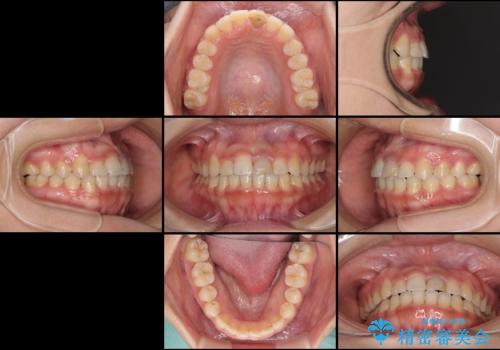

前歯の反対咬合 非抜歯のワイヤー矯正

- 前歯のでこぼこを気にして来院された患者様です。

マウスピース矯正の自己管理が面倒くさいことと、治療を早く終わらせたいとのことで、目立ちにくいワイヤー矯正にて歯列を整えることとしました。

1年半はかかると思っていた治療期間ですが、反対咬合となっている前歯が思いの外早く動き、僅か9ヶ月で終了させることができました。

前歯を気にせず笑えるようになり、患者様には大変満足していただきました。